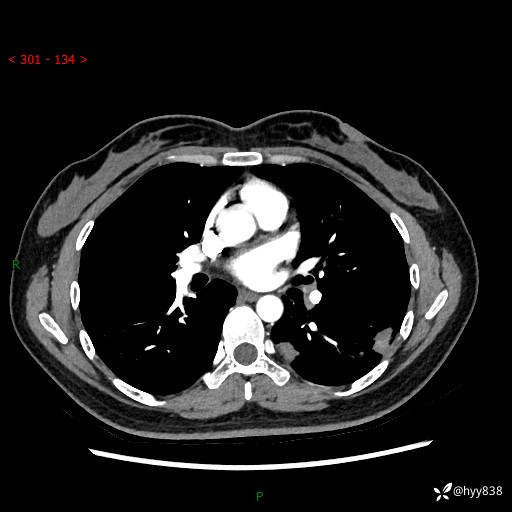

【患者信息】:36岁/女

【主诉】:左侧下胸部阵发性疼痛2周,乏力1周

【现病史及既往史】:患者自诉2周前饮酒后出现左侧下胸部阵发性疼痛,不随呼吸改变,无咳嗽咳痰、头晕头痛、咳血、呼吸困难等不适,于当地第一人民医院查胸部CT提示肺部感染,随后前往我院门诊给予抗感染(左氧氟沙星)治疗1周,自诉胸痛较前好转,感乏力、头晕,偶尔干咳,无咳痰,无发热、畏寒、胸闷、咯血、四肢酸痛、腹泻、腹痛等不适,门诊复查胸部CT提示:左肺下叶感染,病灶较前增加增大,遂以“肺部感染”收入我科。 起病以来,患者精神、饮食、睡眠可,大小便正常,体力体重无明显变化。

【检查】:胸部CT增强(外院平扫)